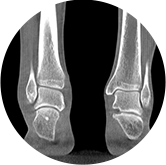

足踝

FOV 250mm

FOV 350mm